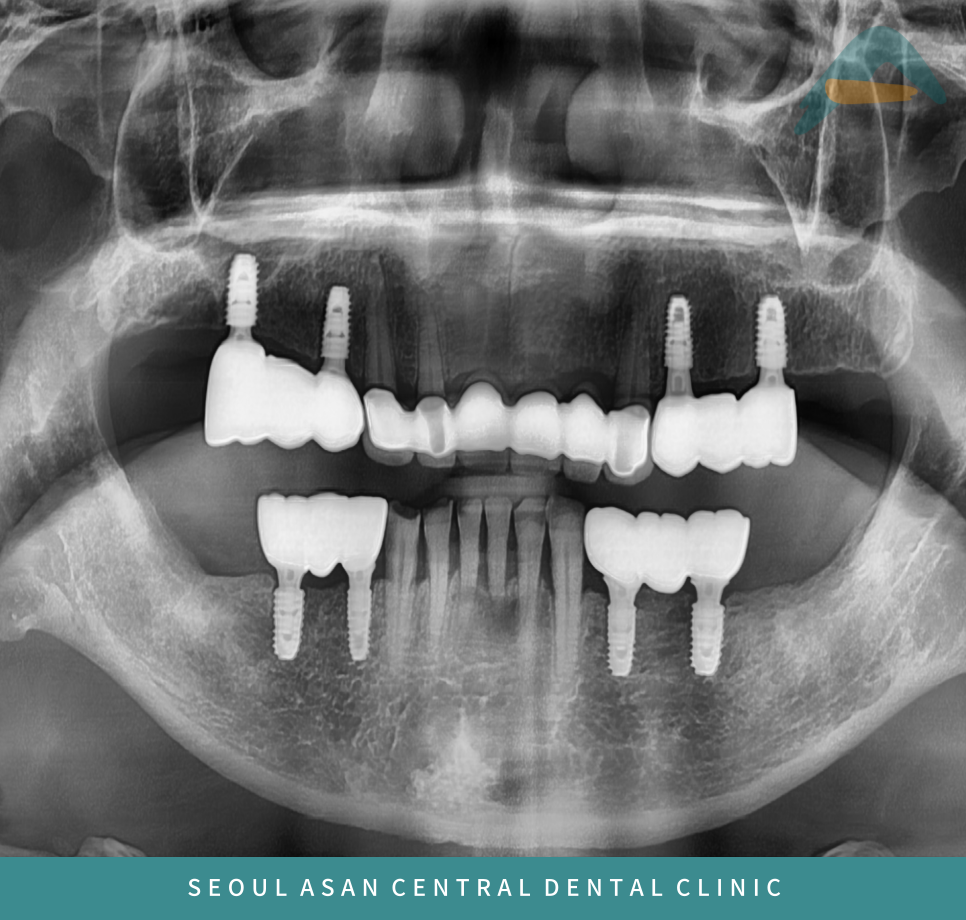

상실된 부위와 발치가 필요한 부위의 치아 수에 맞춰

임플란트를 식립하는 것이 이상적일 수 있으나,

환자분의 잇몸뼈 상태 등을 종합적으로 고려하여

치료 계획을 조정하게 됩니다.

이에 따라 상악 전치부는

기존 보철물이 씌워진 치아를 발치한 후,

인접 치아를 지대치로 활용한 브릿지 보철 치료를

진행하는 것이 보다 적절할 수 있습니다.

임플란트 브릿지란?

상실한 치아 수만큼 임플란트를 식립하는 것이 아니라

지지 역할을 하는 몇 개의 임플란트를 식립 한 후

보철물을 연결해서 씌워주는 방법으로

비용 부담이 적은 반면 브릿지 보철물을 통해

상실한 모든 치아의 기능을 회복할 수 있는 장점이 있습니다.